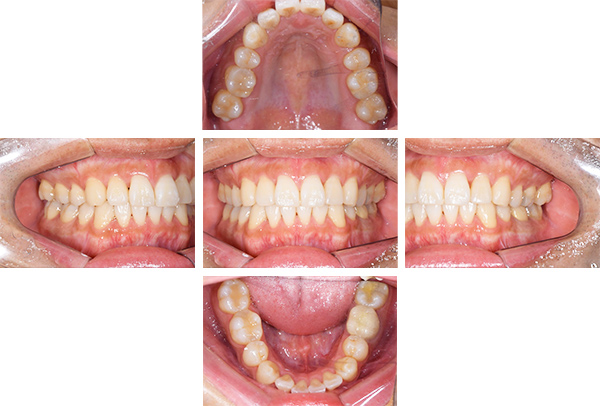

症例写真(治療前)

八重歯が目立ちます。また銀歯もおおく、見た目が気になります。虫歯も散見できます。

症例写真(治療後)

治療後:

矯正治療と虫歯の治療すべて終わったときの写真になります。見た目も最初の頃とは全く違いますし、お口の中もすごく綺麗です。

治療

方針

まずは虫歯の治療を行い、被せ物をする部分は仮歯をいれて矯正を行う。矯正終了後、仮歯の部分を最終的な被せ物に変えていく。また気になっていた銀歯もセラミックに変えて終了となった。

内容

セラミックインレー、オールセラミックプレミアム、矯正